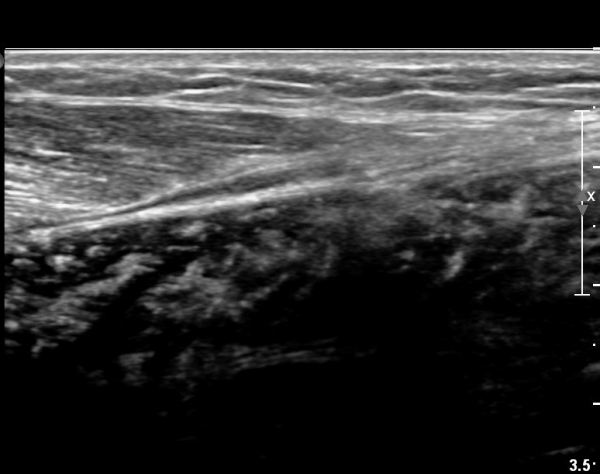

[¹ß¸ñ] simultaneosus tear of GCM and achiles tendon

abrupt leg pain developed during foot volleyball

he walk with severe limping with no weight bearing on rt. leg. on examination, there is local tendernes at GCM and achiles tendon, severe pain with ankle dorsiflexion.

ÃÊÀ½ÆÄ °Ë»ç